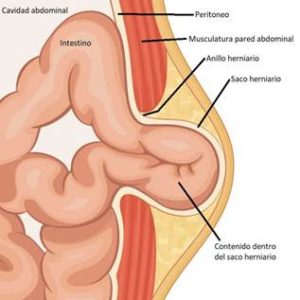

Según la zona anatómica por donde protruya el bulto, la hernia recibe un nombre distinto (inguinal, crural, umbilical, epigástrica, Spiegel, lumbar, hiatal, etc…).

Según la zona anatómica por donde protruya el bulto, la hernia recibe un nombre distinto (inguinal, crural, umbilical, epigástrica, Spiegel, lumbar, hiatal, etc…).